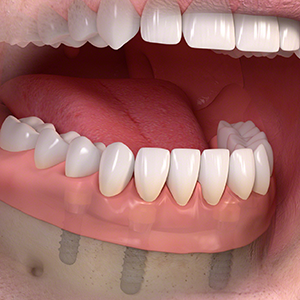

多くの歯を失ったケース

固定式タイプ

・5~8本のインプラントによって自分の歯のように噛めるよう修復

多くの歯を失った場合。

手術でインプラントを埋める。

人工歯を装着します。

インプラント治療で修復。